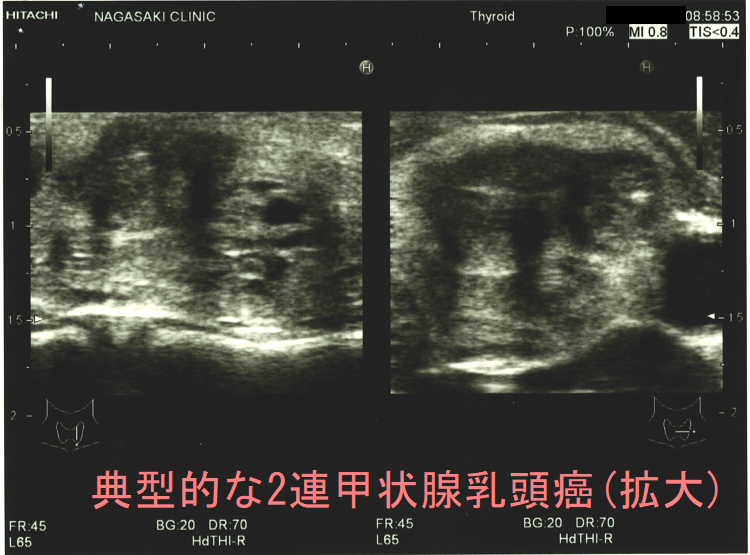

ケース⓪ 典型的な2連甲状腺乳頭癌

甲状腺乳頭癌の超音波エコー画像は境界不明瞭、不整形、粗雑、エコー輝度低く、砂粒状石灰化を伴う。エラストグラフィーで弾性硬~石様硬の硬さが多い。腺腫様結節と鑑別難でも細かい石灰化が異常に多い。解像度高い超音波エコー装置では微細石灰化の音響陰影が無く高エコースポットに見える。粗大石灰化を伴う甲状腺乳頭癌は細胞診で検体不適正率高いが、リンパ節転移・腺内多発・周囲組織浸潤が多い。腺腫様甲状腺腫内部に甲状腺乳頭癌組織が混じっている事も。甲状腺超音波エコー検査では明らかに甲状腺乳頭癌なのに、細胞診で確定診断できない場合もある。

甲状腺乳頭癌の超音波(エコー)画像は、境界不明瞭、不整形、粗雑、エコー輝度低く(黒く見える)、砂粒状石灰化と呼ばれる特徴的な石灰化があるのが典型的です。

増殖した甲状腺乳頭癌細胞はエコーを反射しないため極めて低エコー(黒く)に見える場合が多いです。(あまり黒くない場合もある)